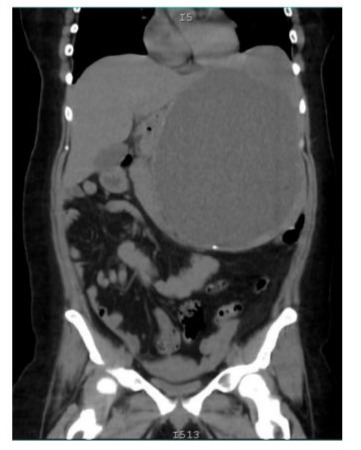

The surgical procedure performed included: (1) careful detumorization to separate adhesions, (2) total splenectomy due to the size of the cyst and the involvement of the splenic parenchyma, (3) placement of two biobag-type drains in the tumor bed and in the pelvic cavity, and (4) prophylactic appendectomy. The surgery was classified as R1 (resection with positive microscopic margins). Intraoperative bleeding was significant, reaching 2400 cc, which required intensive hemodynamic management. The patient was admitted to the ICU immediately after surgery. Close monitoring of hemodynamic parameters was performed, and postoperative anemia was managed. Histopathology confirmed giant splenic cysts with a collagenous wall and reactive epithelial lining. Hematopoietic collection and coagulative necrosis were observed in the adjacent parenchyma. The appendix presented acute peritonitis. Hematological controls two weeks after surgery showed persistent anemia (Hb 10.5 g/dL) and reactive thrombocytosis (630,000 platelets/mm³), common after splenectomy. Twenty days after surgery, a follow-up CT scan was performed, which showed the absence of a spleen with free fluid and inflammatory changes in the surgical bed, persistence of pleural effusion, a probable residual cyst in the gastric fundus measuring 33x58 mm, and retroperitoneal lymphadenopathy (up to 17 mm). After this consultation, follow-up was continued, and at 6 months, a new CT scan showed resolution of the inflammatory changes and lymphadenopathy, as well as the absence of a residual cyst. The patient was referred for an appropriate vaccination regimen against encapsulated organisms (Figure 1).

The follow-up CT scan performed 20 days after surgery revealed important findings that require follow-up. First, the probable residual cyst in the gastric fundus (33x58 mm) could represent an early recurrence or a separate cyst not initially detected; in this regard, Pang et al. (2019) suggest regular imaging follow-up to detect early recurrences [16]. Second, the observed retroperitoneal lymphadenopathy could be a postoperative inflammatory response or indicate an unrelated underlying pathology; close follow-up and possibly a biopsy are recommended if they persist or increase in size. Third, the left ovarian cyst, although probably incidental, warrants gynecologic follow-up, especially considering the patient’s age. Splenectomy in young patients carries long-term risks that need to be considered. Kristinsson et al. (2014) reported an increased risk of infections, thromboembolic events and certain malignancies in post-splenectomy patients [17]. Therefore, it is crucial to: (a) implement an adequate vaccination regimen against encapsulated organisms (S. pneumoniae, H. influenzae type b, N. meningitidis) [18]; (b) educate the patient about the increased risk of Post-Splenectomy Sepsis (OPSI) and the need to seek immediate medical attention in case of fever or signs of infection [19]; (c) consider long-term antibiotic prophylaxis, especially in the first few years post-splenectomy [20]; (d) regularly monitor hematological parameters and consider prophylactic anticoagulation in high thromboembolic risk situations [21].